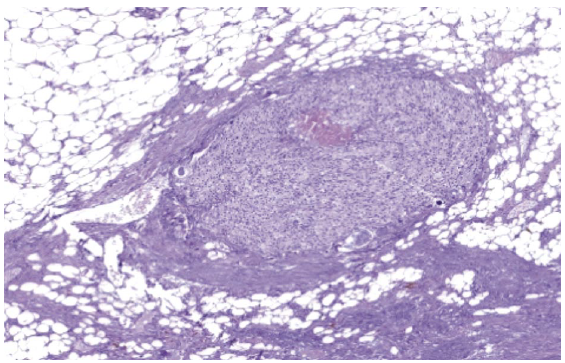

Субстрат новообразования представлен клетками, морфологически сходными с тиреоидным эпителием, часть с онкоцитарной дифференцировкой. Уверенно судить о характере процесса не позволяли отсутствие на клеточном уровне признаков злокачественности, а также абсолютное морфологическое сходство клеток щитовидной и паращитовидной желез (рис. 5).

Рис. 5. Цитологическая картина при пункционной биопсии.

Fig. 5. Cytological picture of the needle biopsy.